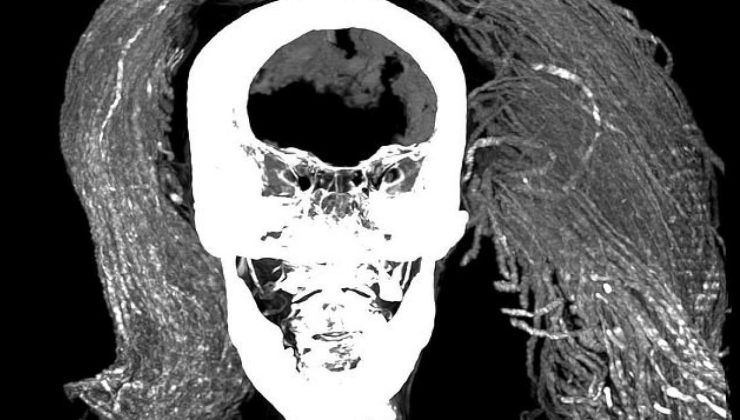

3.500 yıllık sır! Çığlık atan mumyanın gizemi çözüldü…